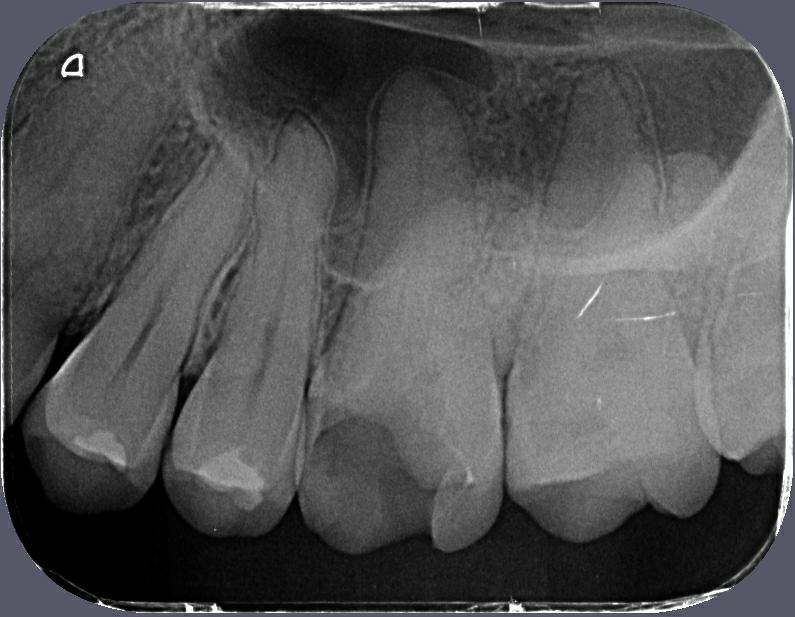

Periapicais